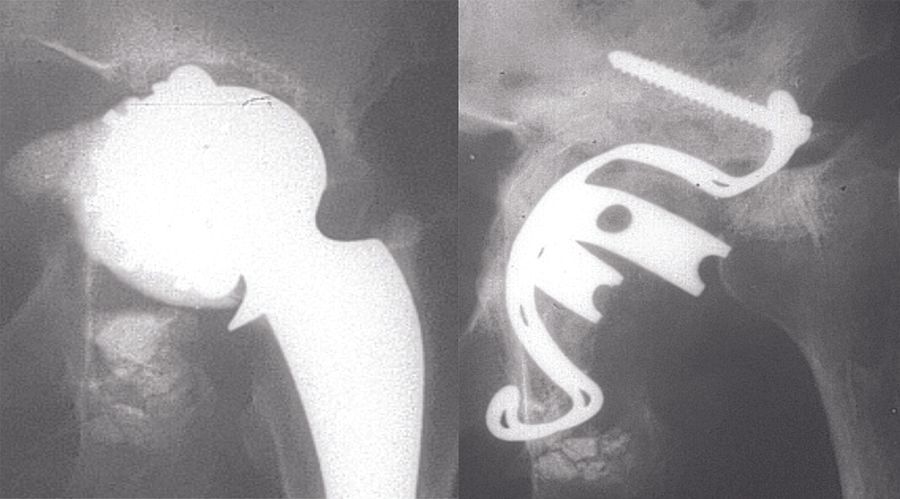

Technique Technique de Reconstruction Cotyloïdienne par armature de Kerboull et allogreffe , Luc Kerboull Espace Médical Vauban, Paris, France , Moussa Hamadouche Centre Hospitalo-Universitaire Cochin Port-Royal - Hôpitaux de Paris, Paris, France , Marcel Kerboull Centre Hospitalo-Universitaire Cochin Port-Royal, Assistance Publique - Hôpitaux de Paris, Paris, France N°268 - Novembre 2017 - Cahier 1 ● 17 min de lecture